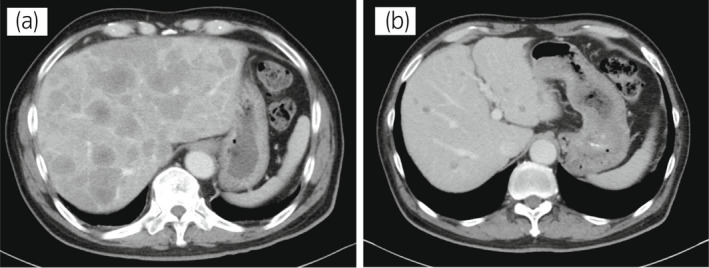

70 歲男性被診斷為轉移性 PC,cT3bN1M1b,Gleason 評分(GS)為 4 + 5 = 9,前列腺特異性抗原(PSA)水平為 40.8ng/ml,3 年前伴有胸椎轉移。 對前列腺進行聯(lián)合雄激素阻斷 (CAB) 治療和質子放射治療 (78.0Gy/39fr)。 PSA 水平降至 <0.01ng/ml,CAB 在 2.5 年后停止。 停止 CAB 五個月后,他出現(xiàn)背痛,PSA <0.01 ng/ml。 計算機斷層掃描 (CT) 掃描檢測到多處肝、骨和淋巴結轉移,神經元特異性烯醇化酶 (NSE) 水平高達 171ng/ml(圖 1a)。 骨轉移活檢顯示神經內分泌前列腺癌 (NEPC) 的診斷(圖 2),患者被轉診至佳學基因合作醫(yī)院。 內分泌腫瘤正確治療醫(yī)生用順鉑、依托泊苷和亮丙瑞林治療。 第三個療程后,轉移部位明顯縮小(圖 1b)。 順鉑和依托泊苷治療 1 年,但患者因神經病變要求停藥。 他開始服用恩雜魯胺。 治療 3 個月后,患者出現(xiàn)背痛和左鎖骨下淋巴結腫大(圖 3a)。 肝轉移保持不變,順鉑治療后縮小。 通過腫瘤正確用藥850基因檢測證實了 BRCA2 突變。根據(jù)基因檢測結果,主治腫瘤科醫(yī)生給予了奧拉帕尼。 三個月后,背痛好轉,淋巴結轉移縮小,確定為部分緩解(PR)(圖3b)。 肝轉移灶保持不變。

圖1:病例1.順鉑和依托泊苷三個療程前后的腹部CT圖像。 (a) 治療前和 (b) 治療后。